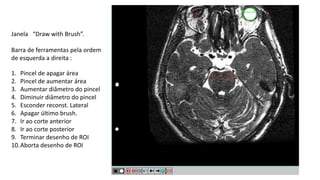

Janela “Draw with Brush”.

Barra de ferramentas pela ordem

de esquerda a direita :

1. Pincel de apagar área

2. Pincel de aumentar área

3. Aumentar diâmetro do pincel

4. Diminuir diâmetro do pincel

5. Esconder reconst. Lateral

6. Apagar último brush.

7. Ir ao corte anterior

8. Ir ao corte posterior

9. Terminar desenho de ROI

10.Aborta desenho de ROI